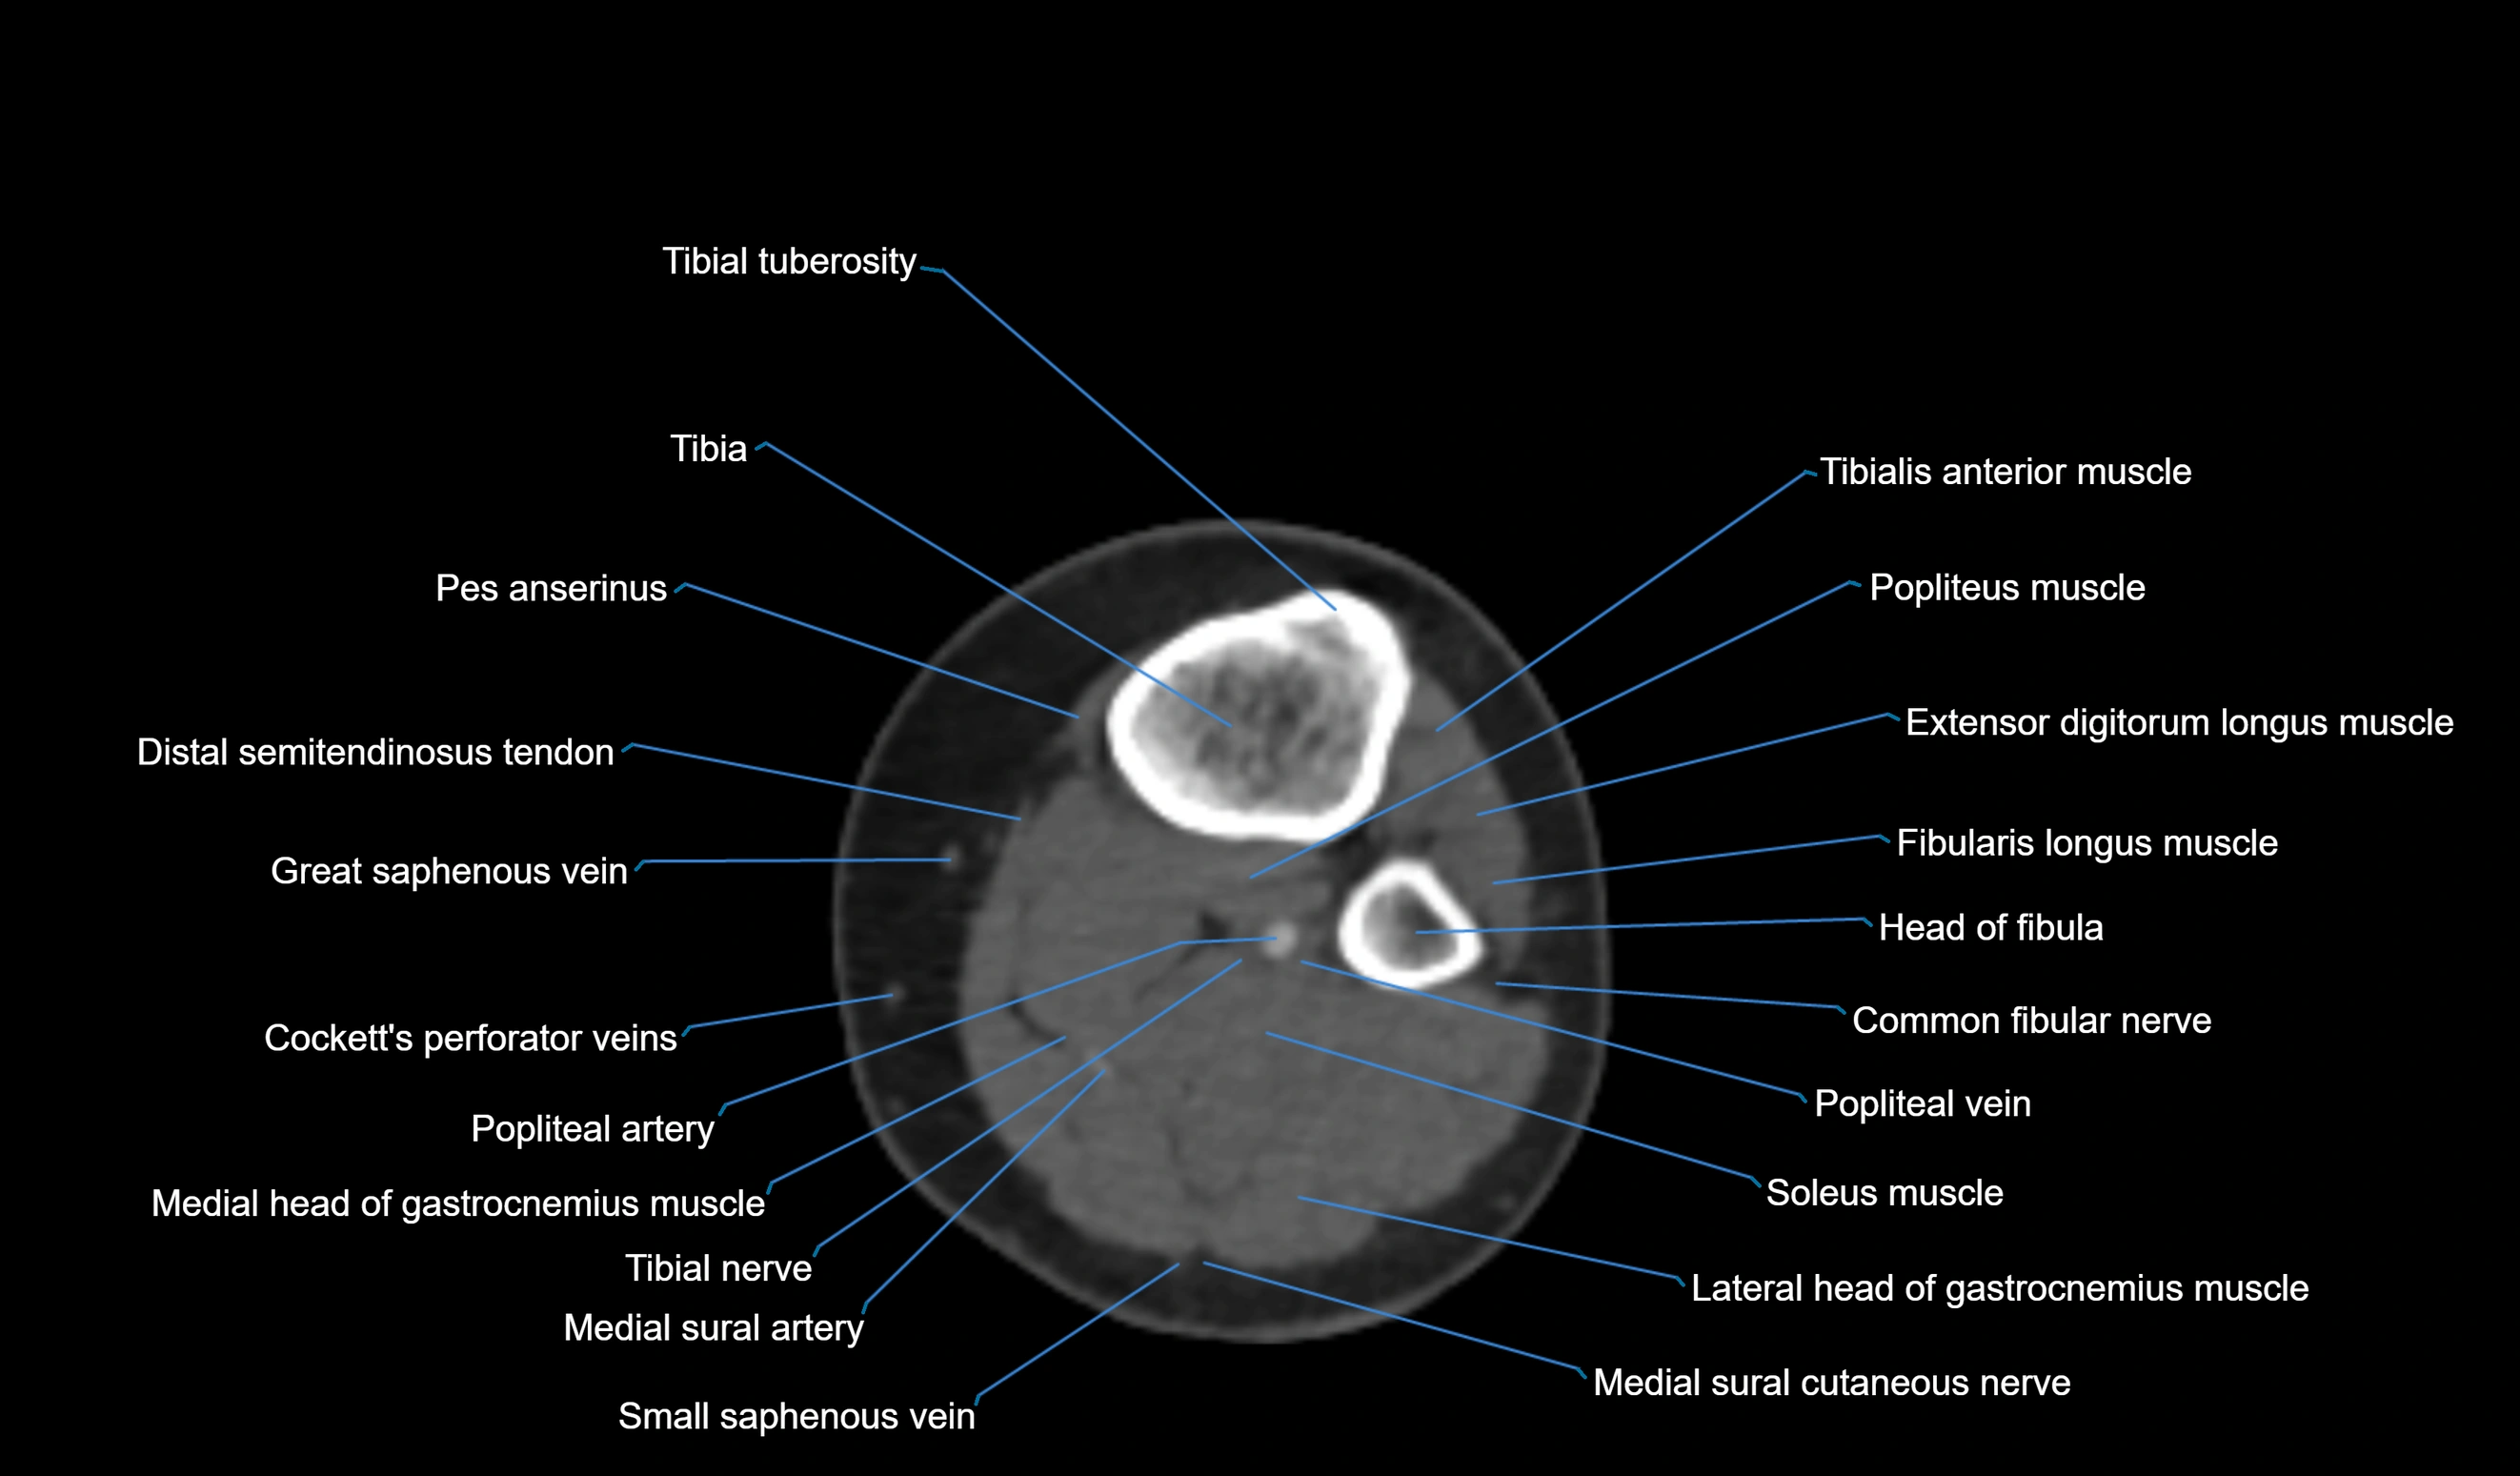

- Common fibular nerve

- Extensor digitorum longus muscle

- Fibularis longus muscle (peroneus longus muscle)

- Head of fibula

- Lateral head of gastrocnemius muscle

- Medial head of gastrocnemius muscle

- Medial sural cutaneous nerve

- Neck of fibula

- Popliteal vein

- Small saphenous vein

- Soleus muscle

- Tibia

- Tibial nerve

- Tibial tuberosity

- Tibialis anterior muscle